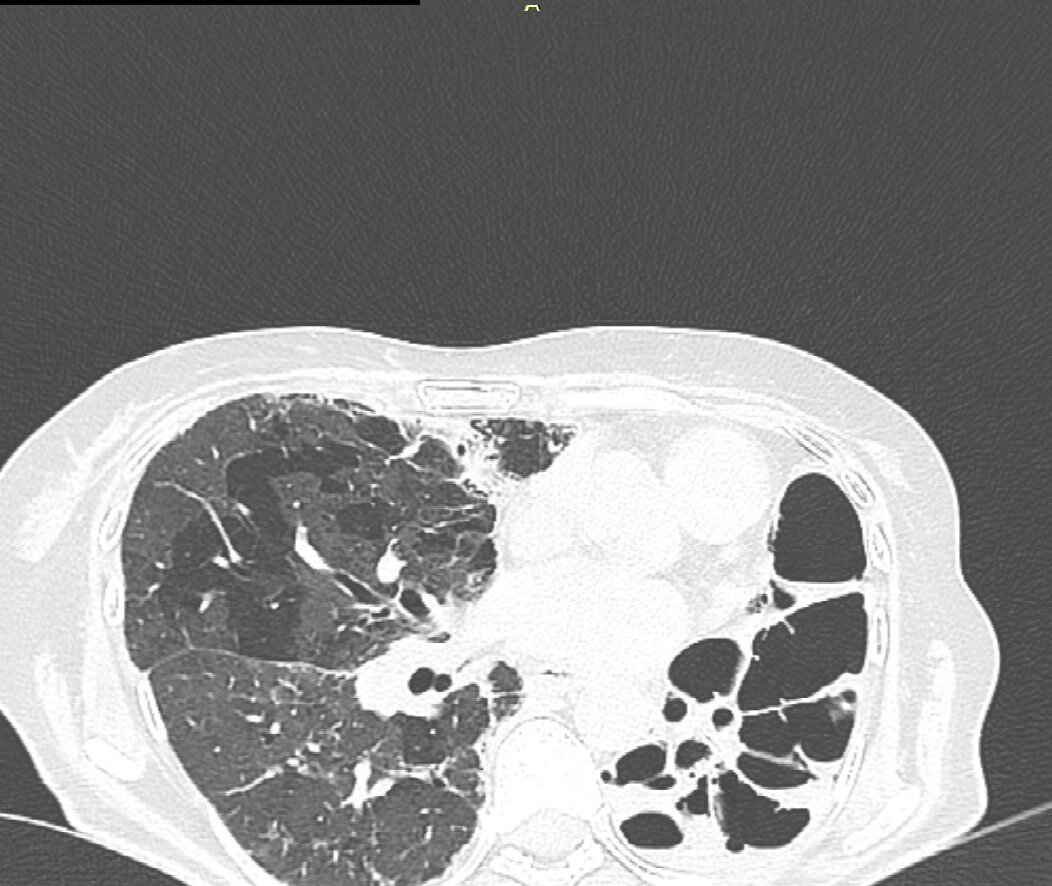

Снимок из серии КТ с диска. Мои лёгкие.